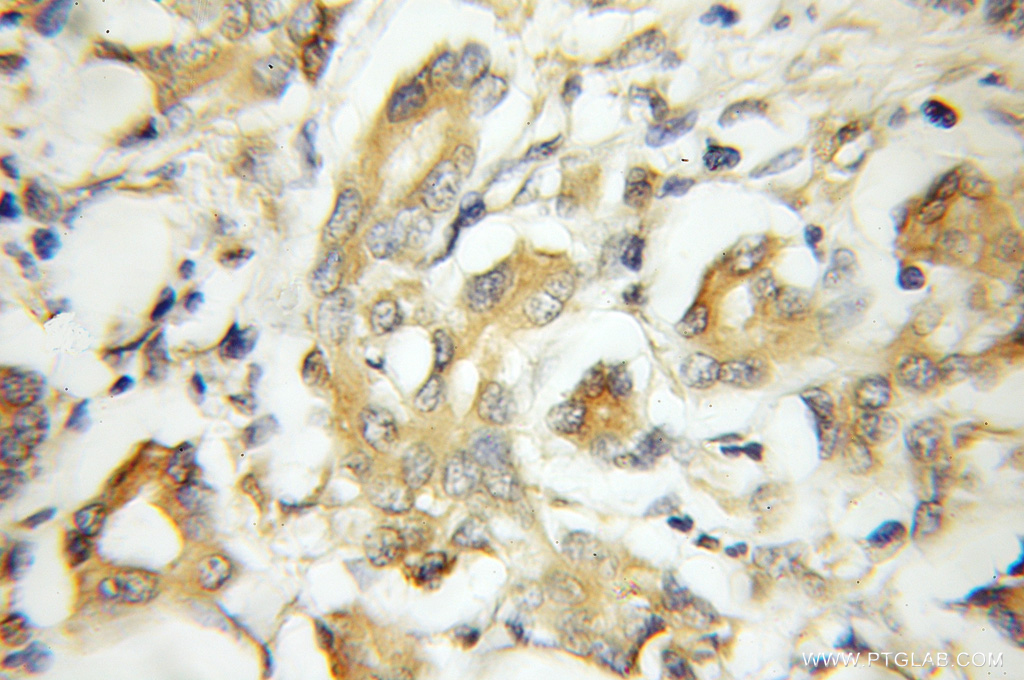

| Positive IHC detected in | human pancreas cancer tissue Note: suggested antigen retrieval with TE buffer pH 9.0; (*) Alternatively, antigen retrieval may be performed with citrate buffer pH 6.0 |

| Immunohistochemistry (IHC) | IHC : 1:20-1:200 |